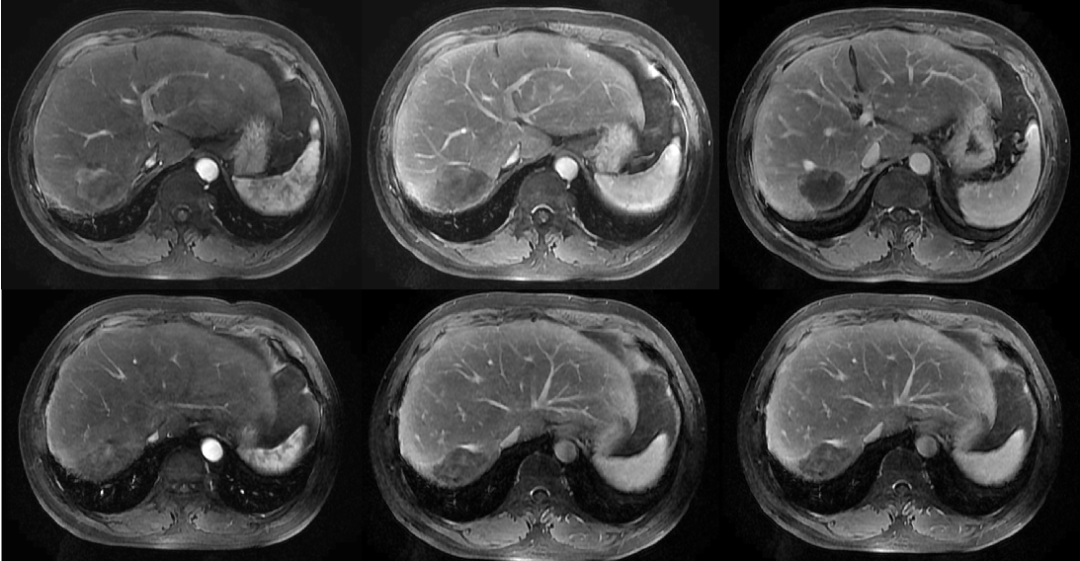

2017年5月15日复查MR,未见明确异常强化(图3)。